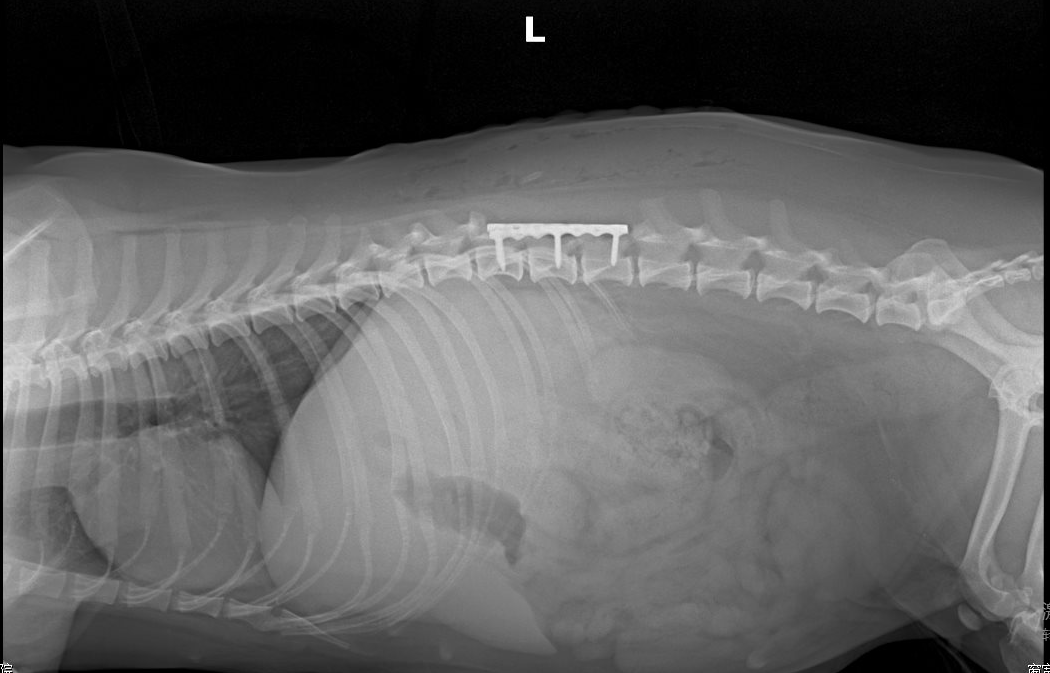

胸腰椎核磁检查

检查部位:胸椎/腰椎MRI平扫检查

检查序列:T1序列,T2序列,压脂序列,压水序列,共218张图⽚⽤于结果判读。

影像所⻅:

1、L1-L2蛛网膜下腔脑脊液连续性消失,椎管内脊髓左腹侧可见T1WI等信号、T2WI低 信号占位,其尾侧(L2中段水平)可见T2WI高信号结构,脊髓受压迫向右背侧移位,L2段 脊髓T2WI信号增强。

2、 T13-L1脊髓腹侧可见T1WI等信号、T2WI低信号结构。3、T13-L2、L4-L5椎间盘呈T2WI低信号。

影像印象:

1、汉森II型椎间盘突出(L1-L2),压迫脊髓及左侧神经根,后段脊髓损伤/水肿,出 血可疑,结合临床评估。

2、轻度汉森I型椎间盘突出(T13-L1)。

3、胸腰椎多处椎间盘变性。

影像检查⬇️